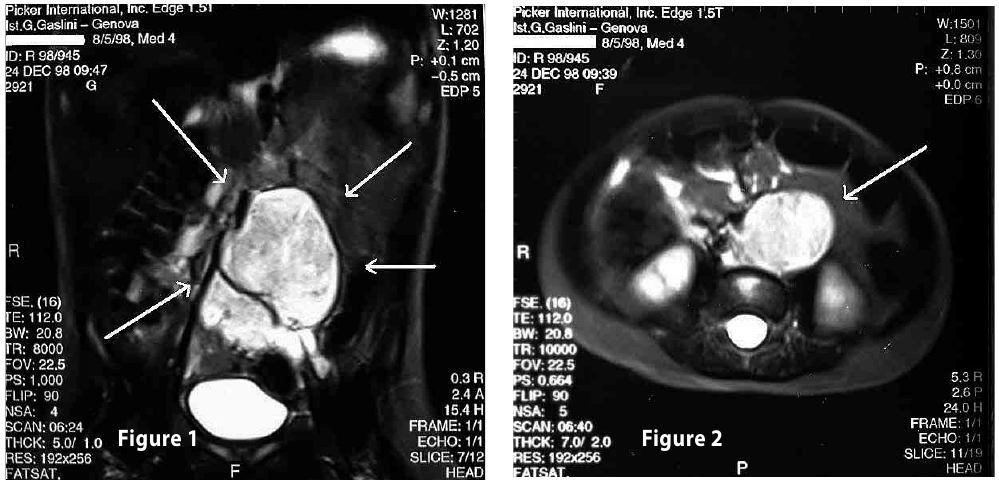

Complete objective response of neuroblastoma to biological treatment.

Figure1

Figure2